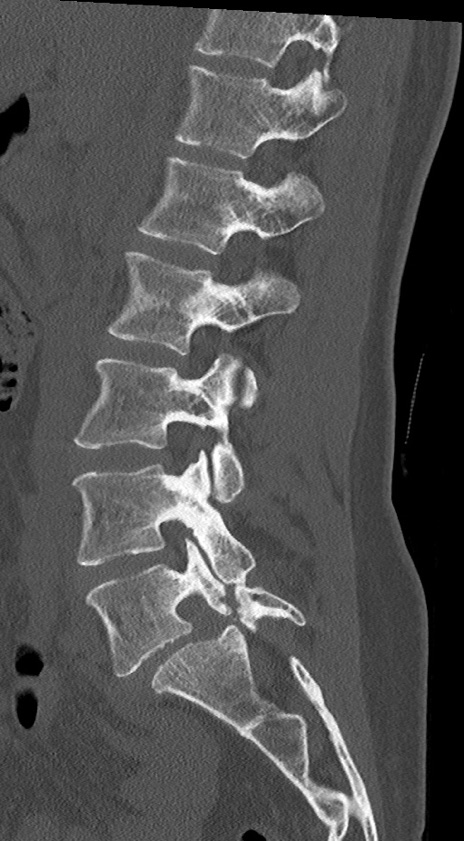

【整形】TIPS症例4 腰椎CT(矢状断像)

腰椎CT